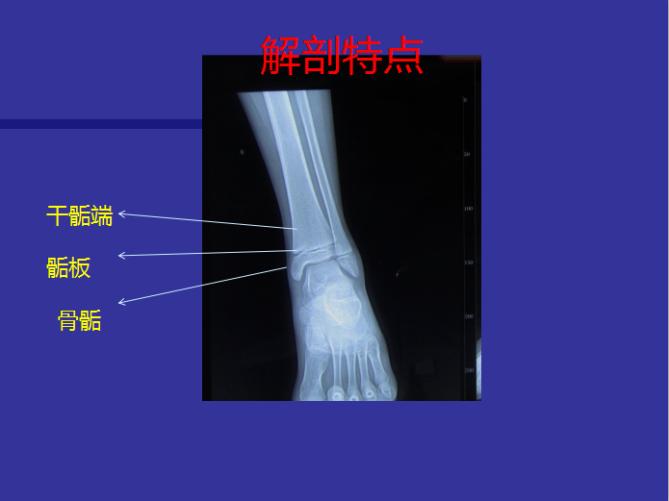

近日,沈阳市骨科医院小儿骨科医生于泓淼来到中国邮政储蓄牛心垛营业所,为辖区百姓讲解"儿童骨骺损伤诊断与治疗"的相关知识。于医生介绍,骨骺损伤是涉及骨骼纵向生长机制损伤总称。包括骨骺、生长板、Ranvier区、与生长相关的关节软骨及干骺端损伤。

儿童骨骺损伤是儿童常见及特有的损伤,约占儿童骨折的三分之一,骨骺的损伤可能带来肢体的变形、不等长等问题。尽管骨骺的损伤会产生较严重的问题,但如果有专业的小儿骨科医生处理得当,其修复的结果往往还是令人满意的,所以骨骺损伤的诊断与治疗决定了预后。